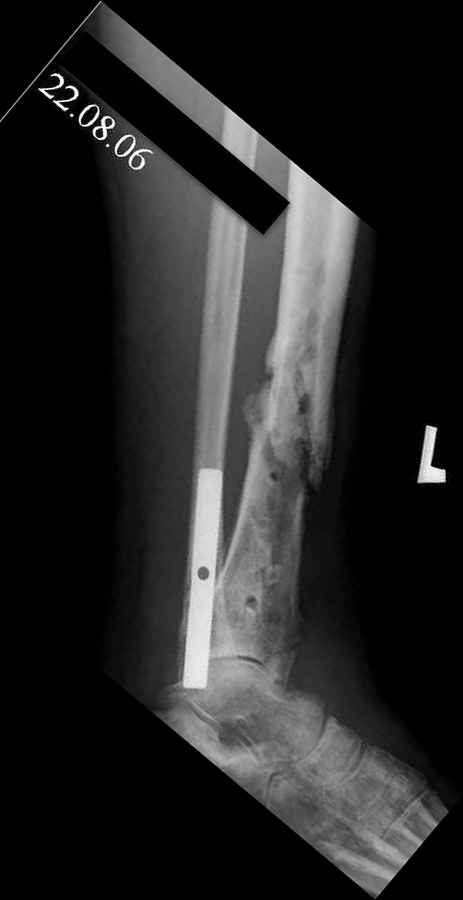

дефекта: за счет удлинения концов б\б кости или тибиализации м\б. На начальном этапе фиксация только в аппарате, в последствие для удержания достигнутого можно перейти на фиксацию интрамедуллярным штифтом (см. вложенные файлы)

Как дополнение высылаю снимки и фото конечности, чтобы Вы могли оценить состояние м/т, и течение заболевания.

Кстати на предоперационных снимках видно, что Ваш пациент имел Сегментарный перелом на границе верхней и средней трети большеберцовой кости и средней трети большеберцовой кости. Непонятно почему был удалён средний сегмент перелома.Почему в течении такого большого времени не предпринимались попытки для замещения деффекта.

Судя по месту расположения свища, наличия литического учаска в проксимальной части дистального фрагмента на последнем снимке, и, наличие в этом месте стержня Шанца на послеоперацционном снимке, причина остеомиелита у Вашего пациента спицевая.